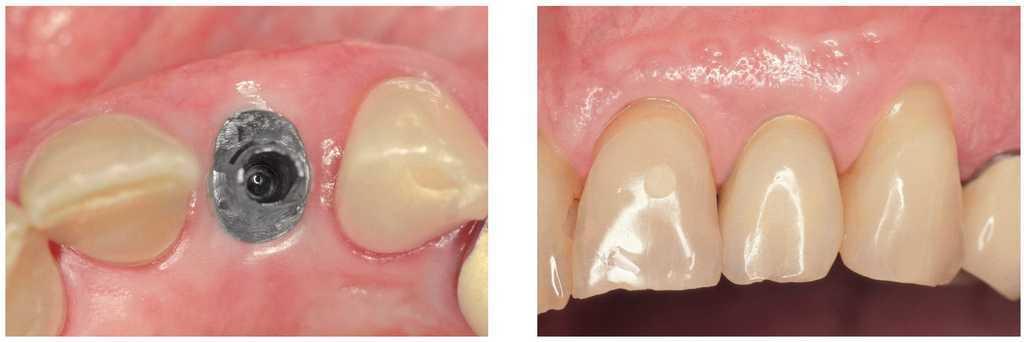

Figura 2a. Ausencia del diente 12, dientes adyacentes sin caries.

Figuras 2b y 2c. Puente adhesivo de cerámica sin metal de una aleta desde incisal (b) y vestibular (c).